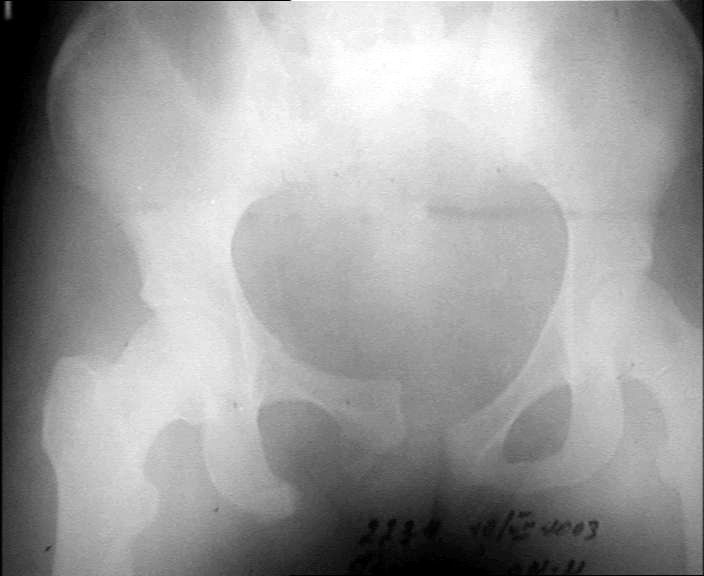

Для уточнения характера повреждений задних отделов таза необходим дополнительный снимок таза в косой проекции (inlet).

Если повреждение таза ротационно нестабильное, то достаточно сдавить крылья подвздошных костей аппаратом и затем провести синтез лона пластиной

Если имеется вертикальная нестабильность, то без фиксации задних отделов не обойтись, например илиосакральный винт или кольцевой аппарат.

Кликните для загрузки файла inlet.jpg